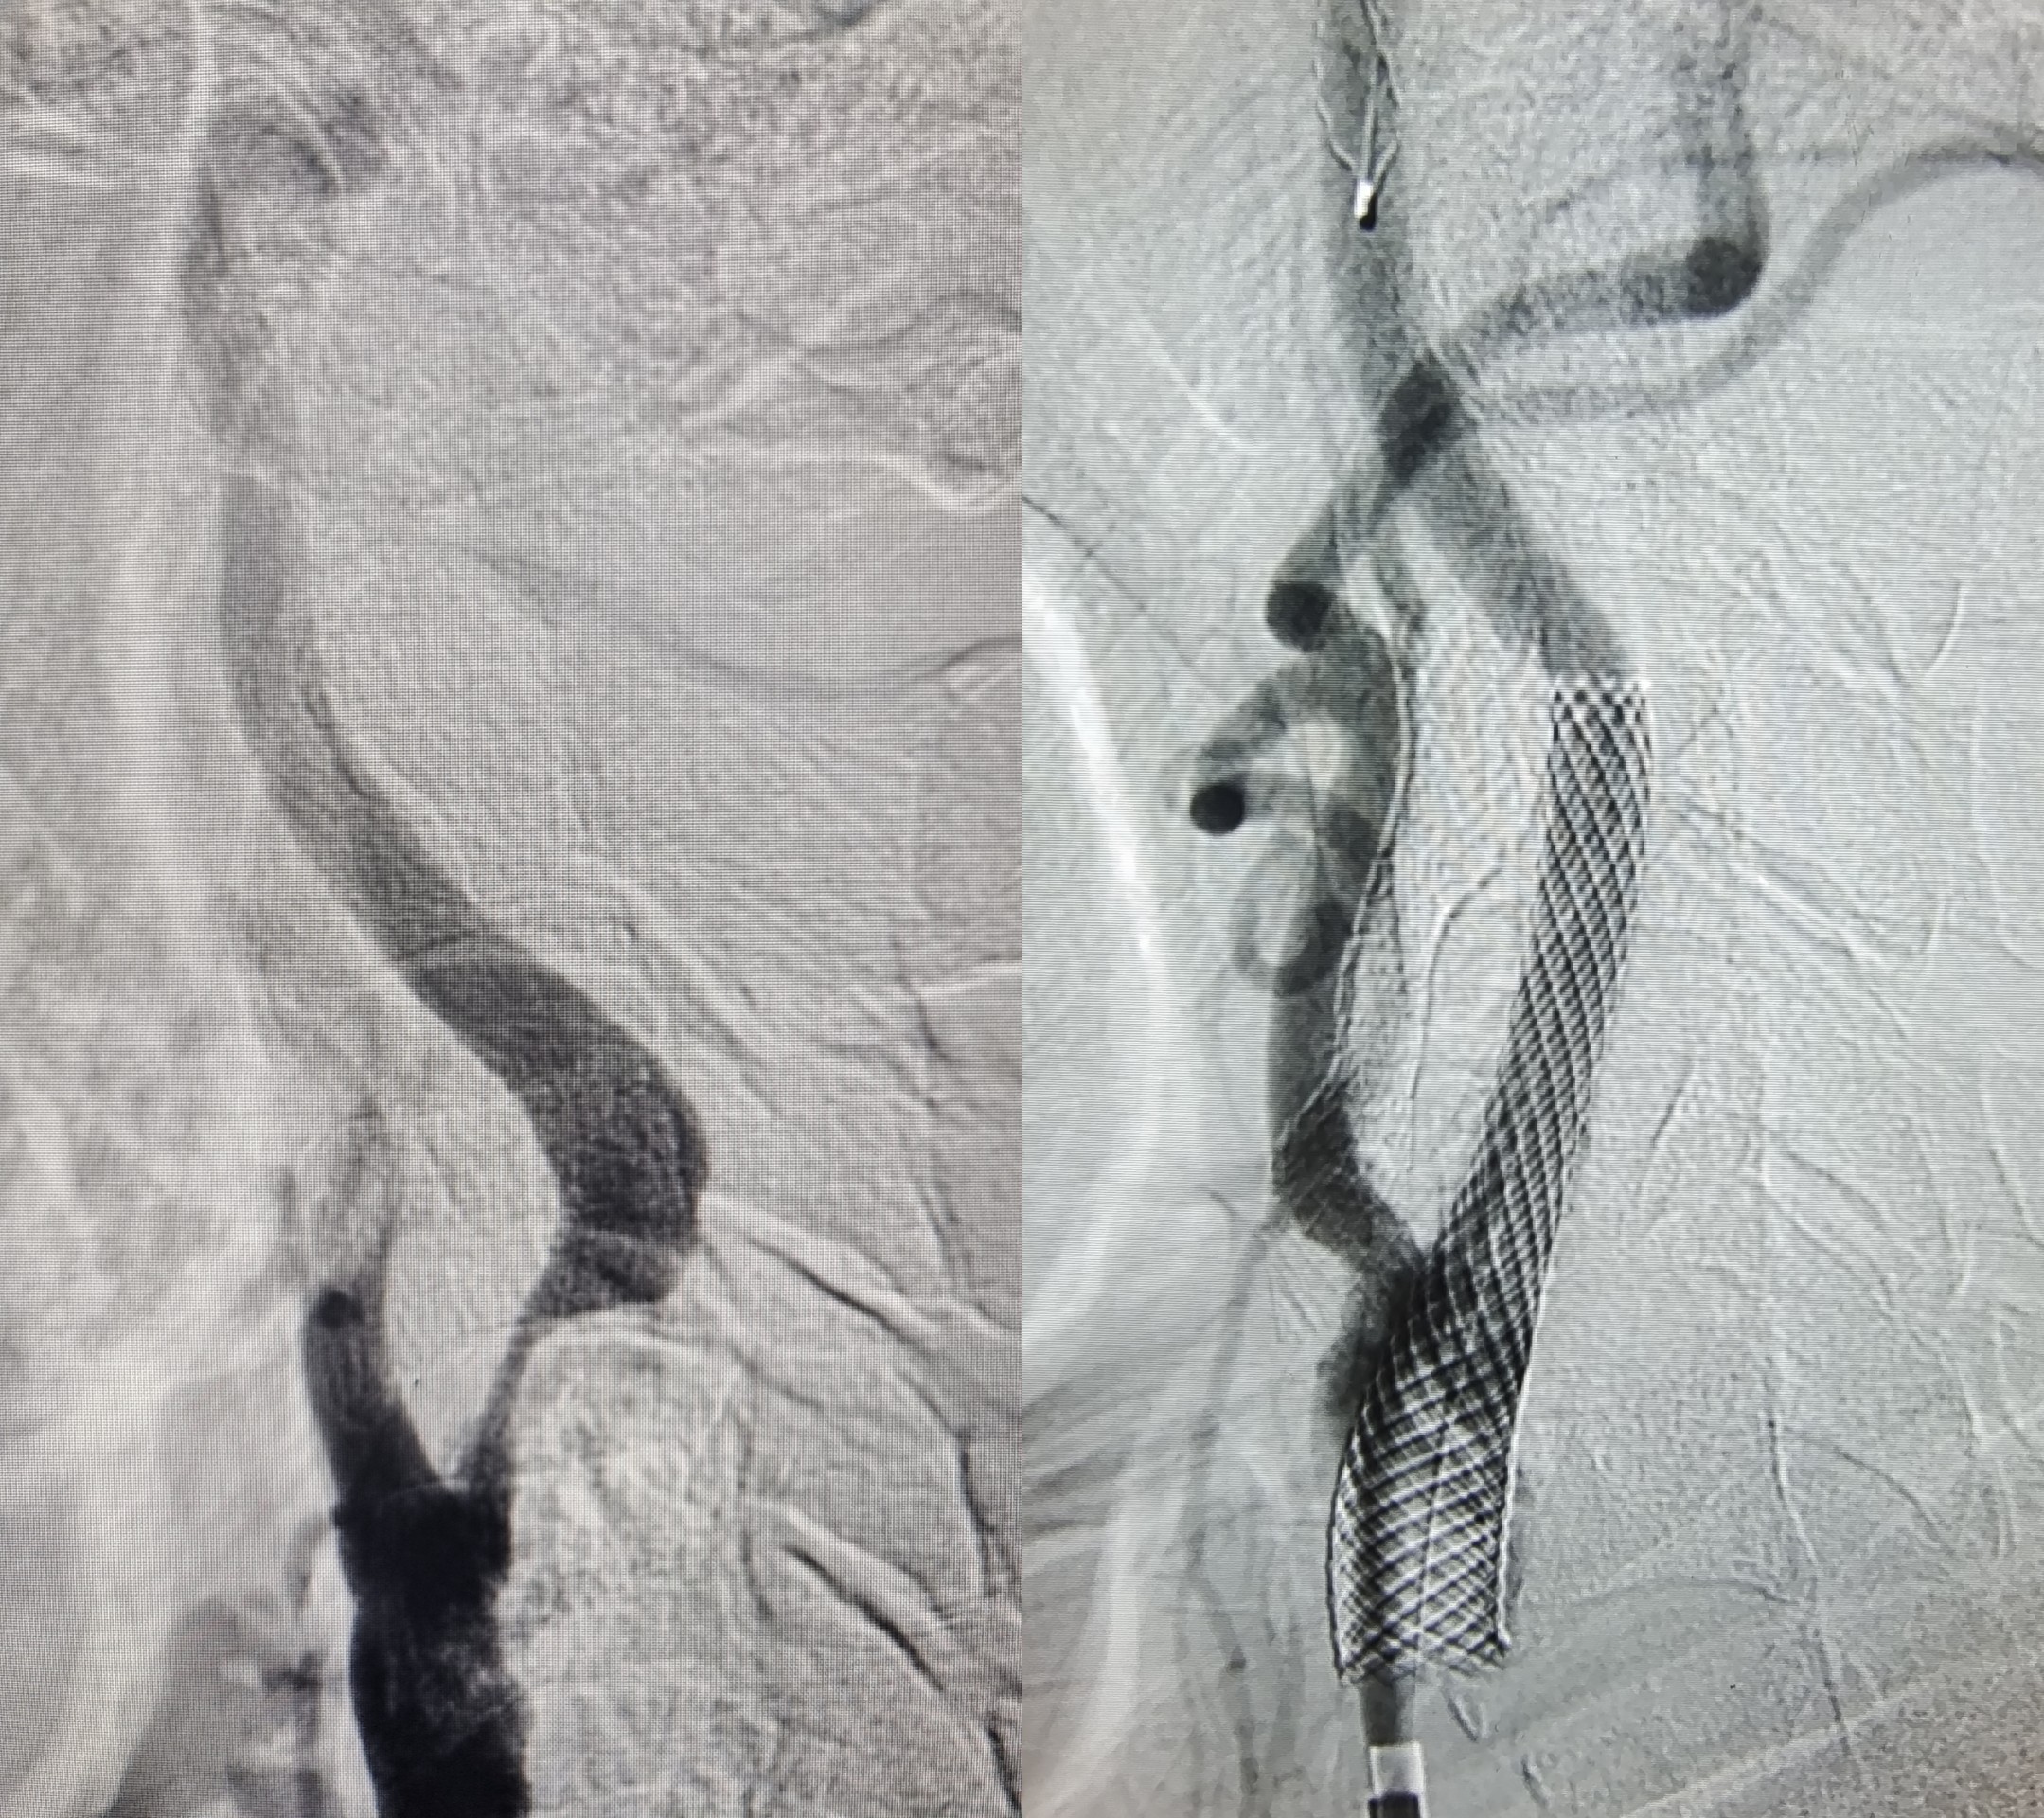

在征得患者及家属同意并完善相关术前准备后,王光胜副院长带领卒中中心团队为李大爷实施脑保护伞下颈动脉支架置入术。术后造影显示颈内动脉扩张良好,远端显影良好。

▲图为患者术前、术后血流图